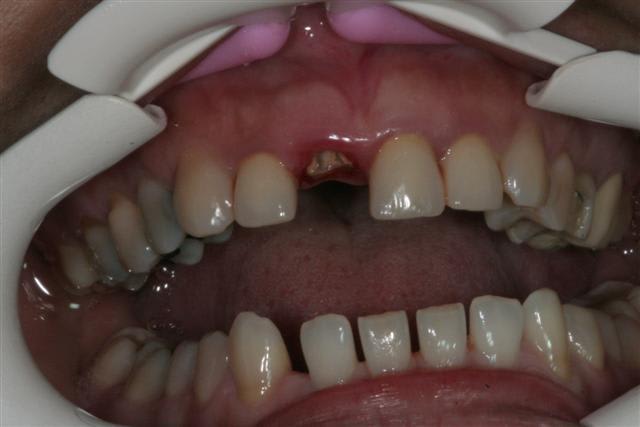

la patiente a en bouche des ceramiques faites depuis plus de 15 ans(made in USA)avec les traitements s'y référents

seule la 11 a cassée(due au deplacement de l'antagoniste? peut être,sans doute)

je ne me suis pas acharnée à retirer le cône noyé ds la pâte(acryl? ou thermafill mais cela existait il à l'epoque?) vu l'absence d'image apicale et.... le fait que je n'y suis pas arrivée:)

tort? raison?

on verra mais à un an 1/2(IC et prov posés en nov 2005) pas gd chose ne se passe

la fracture était basse en vestibulaire,la gencive assez fine et je n'ai pas "senti" le remodelage gingival sur la provisoire(qu'en termes corrects ma peur de rater peut être exprimée:)

d'où l'empreinte avec bague de Cu pr aller chercher les limites

la CCM est en prov de luxe

(ça tombait bien,la teinte est moyenne,bien qu'elle passe mieux en bouche que sur la photo:le flash?)